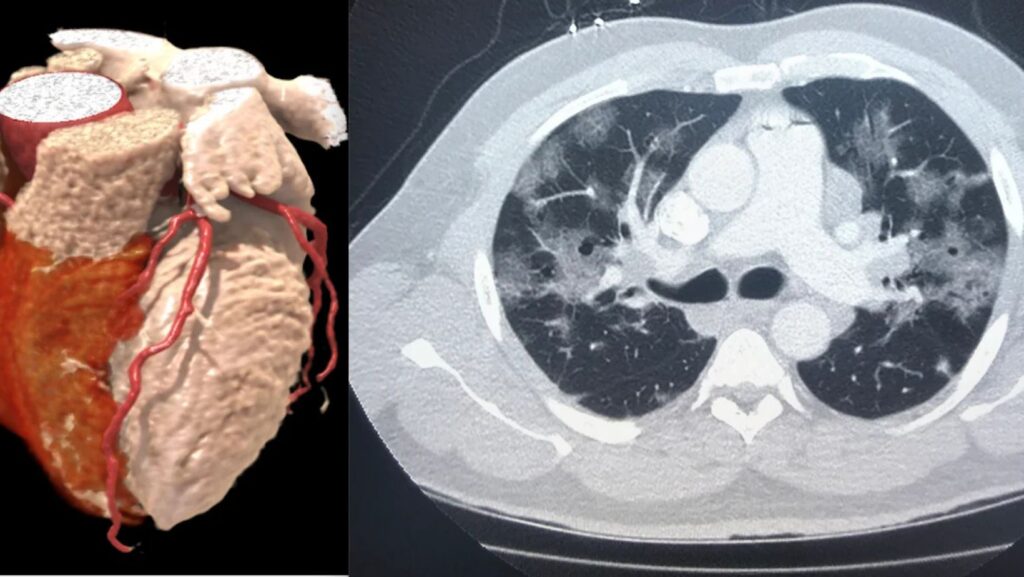

SPECT MPI is a widely used tool for detecting coronary artery disease, offering detailed images of blood flow to the heart. However, for accurate results, it traditionally requires an additional CT scan for attenuation compensation (AC), which corrects for signal weakening as it moves through body tissue. Heart images can be distorted without this correction, leading to potential misdiagnoses.

The CTLESS method replaces the need for a CT scan by leveraging deep learning and physics-based modeling. It estimates a synthetic attenuation map directly from the emission scan, allowing AC without requiring a separate CT scan. This not only improves diagnostic accuracy but also reduces radiation exposure and costs.